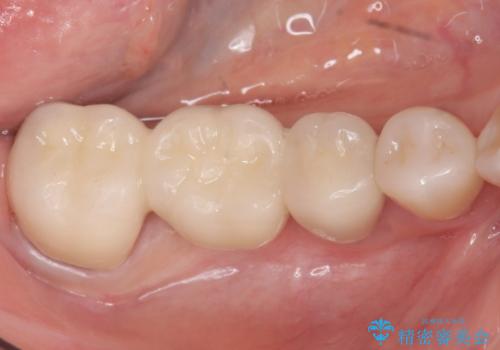

ブリッジの自然な見た目と咬み心地にご満足頂けました。

メタルボンドクラウン(外側はセラミック、内側はメタル)では舌側の歯頚部がメタルの場合が多いのですが、すべてセラミックで覆うフルベイク仕上げでオーダーし、審美性を追求しました。

クラウンの種類:メタルボンドクラウン エコノミー フルベイク